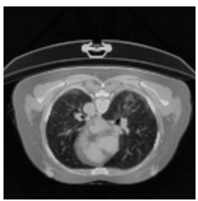

In Table 6, a comparison of the ground truth and prediction results of each model is presented in 2D, along with the 3D projection of each model. The visual analysis of the predictions provides additional insights into the performance of each model. The visualizations demonstrate that Attention UNet captures the intricate details of the lung construction more accurately, resulting in more precise segmentation of the infected areas compared to other models.

Table 6.

Comparison of ground truth and model prediction results using UNet, LinkNet, Attention UNet, UNet 3+, and TransUNet.